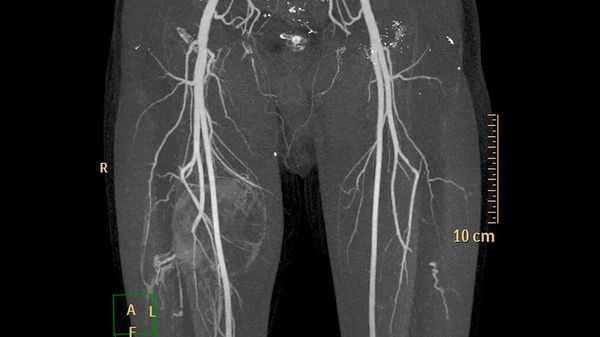

Микрохирургическое удаление мальформации - в этом случае выполняется трепанация черепа, с последующем иссечением мальформации. Является самым радикальным, но не самым безопасным методом, особенно для больших или гигантских, а также располагающихся в функционально значимых зонах мальформаций. Эндоваскулярная эмболизация мальформации - выполняются путем прокола артерии, чаще бедренной (в паховой области), с последующим заведением специальных катетеров в тело артериовенозной мальформации и заклеивания ее изнутри с помощью специальных клеевых композиций. Лечение может быть как одномоментным, если мальформация небольшого размера, так и многоэтапными растягиваться на несколько лет. Количество этапов зависит от размера мальформации, ее строения, особенностей ранее проведенных операций. За одну этап стараются выключать около 30% объема мальформации, хотя понятие процента эмболизации носит условный и субъективный характер. При этом метод эффективен в 80-90% для маленьких, 40-50% для средних и только в 10-30% для больших или гигантских мальформаций. Комбинированное лечение - возможно сочетание первых двух методов. В этом случае проводится эндоваскулярная эмболизация (на сколько это возможно технически и безопасно) с последующим ее микрохирургическим удалением. Лучевая терапия - возможно облучение на аппаратах гамма-нож, линейном ускорителе, протонном пучке. Как правило, это касается мальформаций размер которых не превышает 3 см и при условии отсутствия высокоскоростных артериовенозных шунтов в ее теле. Эффективность метода оценивается не сразу, а в течение 2-3 лет с момента облучения. В последующем выполняют контрольную ангиографию, по результатам которой и принимают решение о дальнейшей тактики лечения.